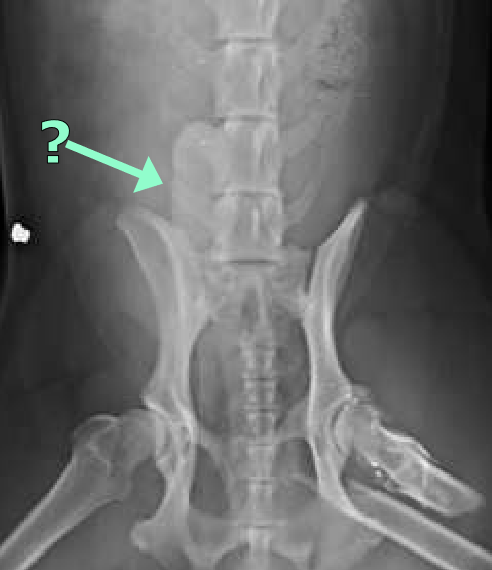

Ventral abdominal wall

Lateral abdominal wall

nipples

prepuce